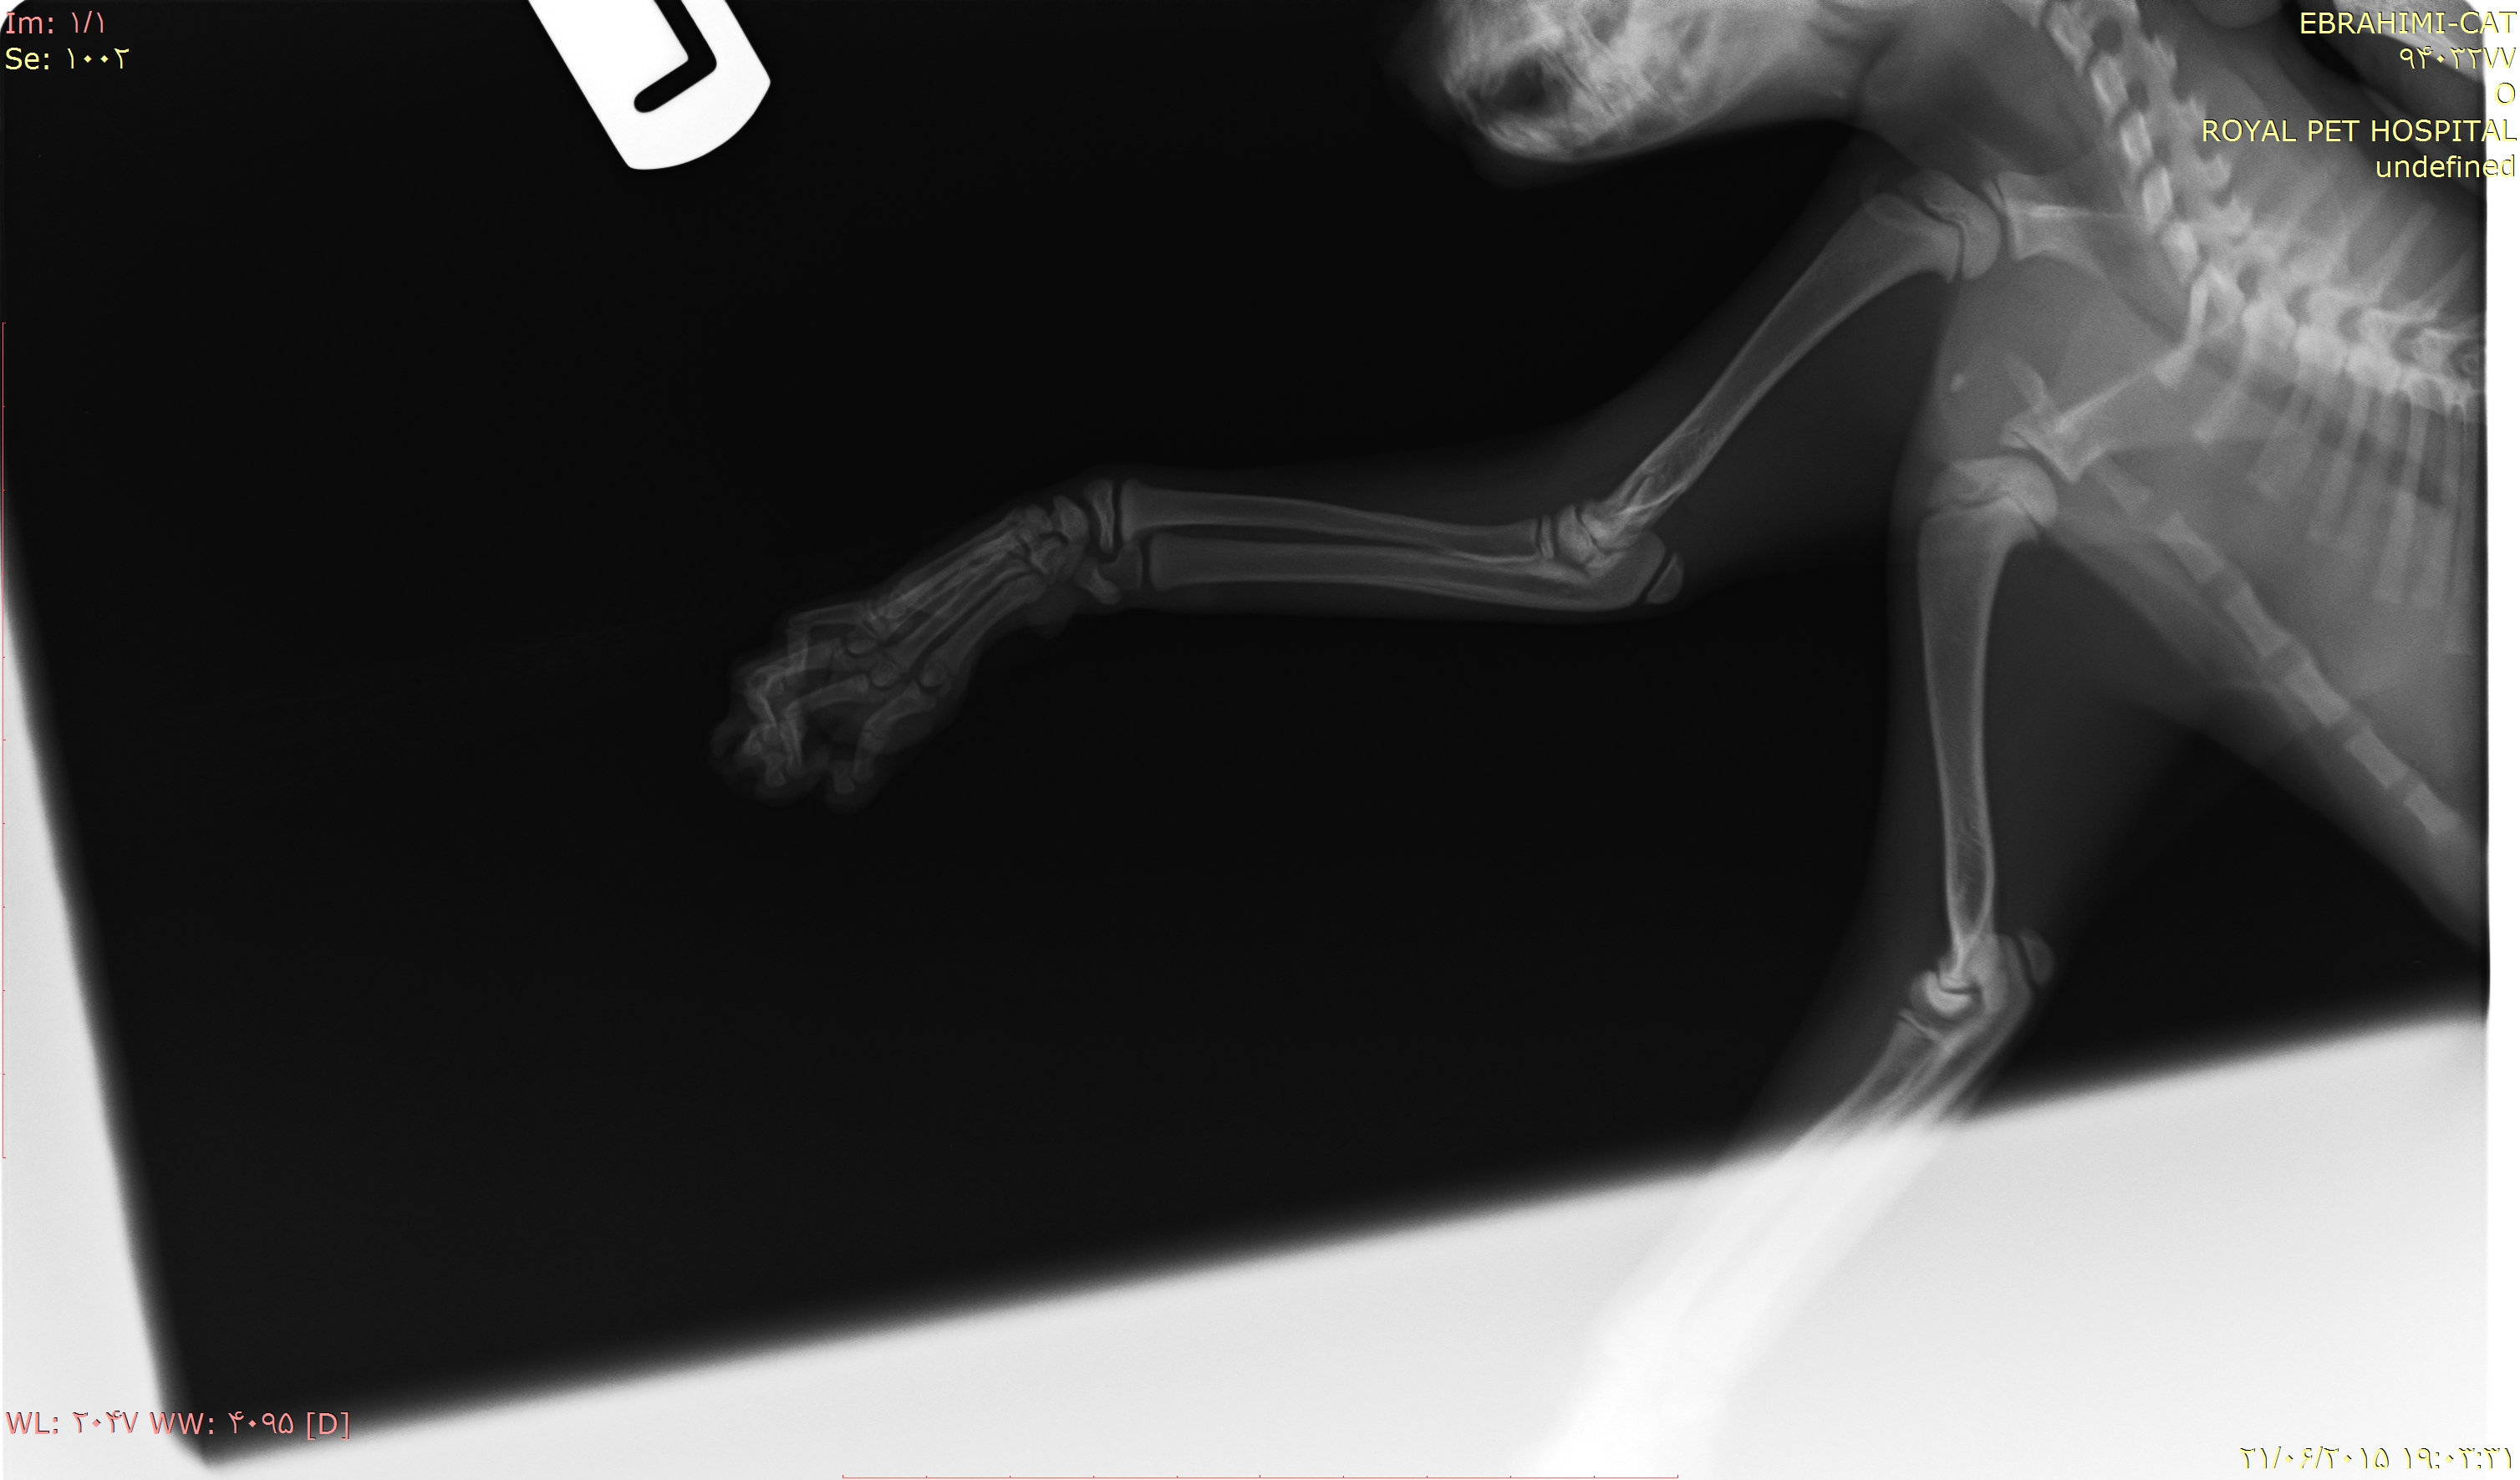

باسلام و احترام

گربه دوماه و نیمه ی من بعلت سقوط از ارتفاع دچار صدمه دیدگی شده.میخواستم نظرتون رو درمورد عکس هایی که ضمیمه میکنم بدونم.آیا نیاز به عمل جراحی هست یا خیر؟ باتشکر( این سوال 10 سال قبل مطرح شد و 10 سال قبل به این سوال پاسخ داده شده است. )